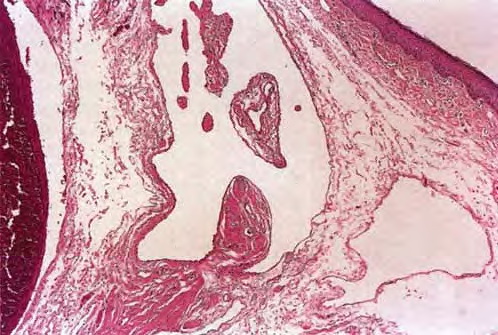

Read MoreVerruca palmoplantaris = الثؤلول الراحي الاخمصي